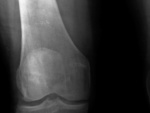

Женщина 1950 г.р.Направлена на рентгенографию по поводу артроза коленных суставов. Предыдущих снимков нет, С 2000 года в карточке нашла записи хирурга(артрит, артроз левого коленного сустава).В рентгенологических протоколах артроз. Мне не понравился правый коленный сустав, а именно дистальный метафиз. Похоже на остеоид-остеому?

И не только, м.б. и просто эностоз, и инфаркт, и много кто. А прямого нет?

Да конечно прямого, извините. Уже поправил.  Похоже, если видеть только какое-то разрежение, вокруг очага уплотнения. Пателла как-то не сильно конгруентна, признаки 2стад. артроза имеются.( м.б. отсюда боли?)

Да, артроз бесспорен, но меня больше интересует, что это такое в метафизе?!

Мой диф ряд такой энхондрома, хондросаркома, инфаркт костного мозга

Энхондрому напоминает. А остеоид-остеому - нет.

Спасибо огромное, так более четко,особенно в боковой проекции.Никаких нвых предположений?Похоже на остеоид-остеому,но плотная часть какая-то неоднородная,склеротический ободок присутствует.А может это киста старая?

Может быть, много чего... Кисты версия заинтриговала. Я такого себе бы сейчас не позволил уже.) Насчёт остеоид-остеомы - вместо склеротического ободка здесь ободок локального пороза - то есть нет в гнезде типичного яйца.)

Согласна,классического плотного центра нет,  но образование имеет достаточно четкие контуры ,периферические отделы намного плотнее, чем центральная часть, как скорлупка, а за ней уже идет зона разряжения костной структуры.Короче говоря, вызвана на дообследование, будем переснимать на цифру...